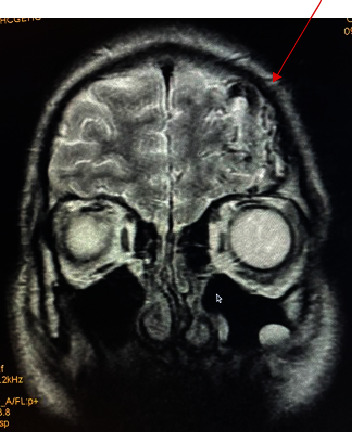

Background: In psychiatry, anatomical abnormalities are sometimes forgotten, and this can mislead doctors into thinking that the diagnosis is purely psychiatric. A physical examination is important whenever it is possible. Even though cerebral arteriovenous malformations (cAVMs) are rare and can go unnoticed, in some cases they can cause clinical symptoms, which is a complication. Case Presentation. In this case, we describe a patient with no prior medical or psychiatric history having a cAVM diagnosed after showing psychotic symptoms (delusion and disorganized thoughts and behavior). The deep 4 × 5 cm cAVM was discovered after admitting the patient to psychiatric ward, the neurological cause has been considered after a recorded seizure, which brings the following question: Is the clinical presentation a direct result of the cAVM or is it postictal?

Conclusions: An abnormality leading to another, here is how we could describe our patient's psychopathology leading to psychotic symptoms. The two hypotheses explaining this case report have a low rate of occurring making this a rare case. Either way, neurological cause cannot be overlooked even if the clinical presentation is typical.